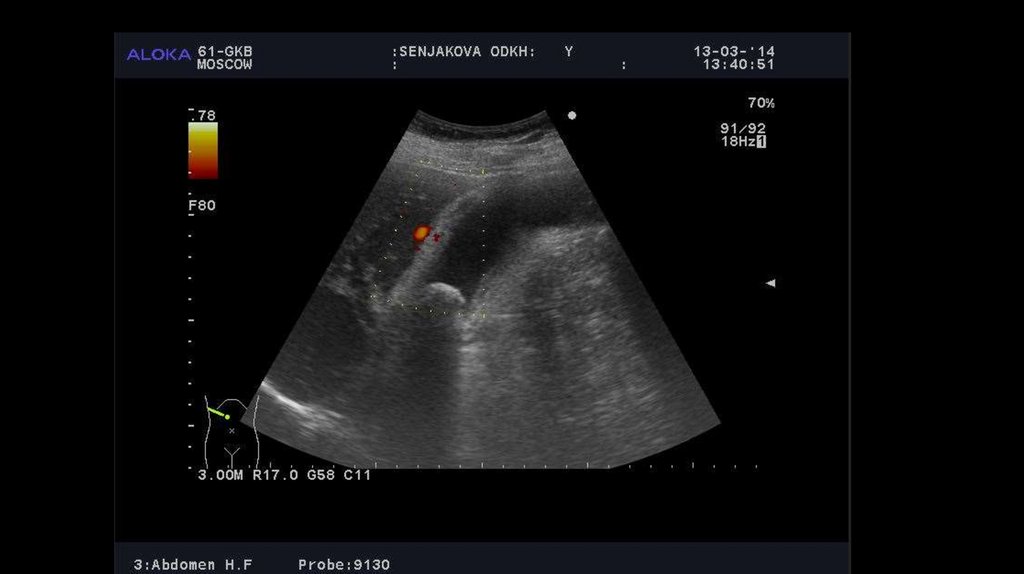

4. УЗИ органов гепатобилиарной системы

УЗИ и рентген. Рентгенологическое исследование позволяет обнаружить различные признаки морфологических или

протоков возможно радиорентгенохромодиагностическим методом. С помощью УЗИ удается установить отсутствие

конкрементов, а также дать оценку сократительной способности и состоянию стенки желчного пузыря (признаком

хронического холецистита является ее утолщение на 4 мм и более).